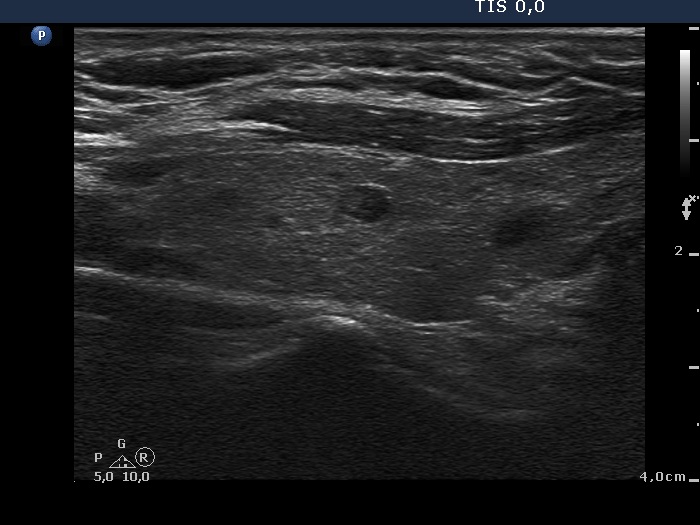

The operated thyroid - case 318

Six months after surgery (ultrasonographic picture 2)

Right lobe, longitudinal scan. The thyroid contains several small hypoechogenic areas without any clinical or oncological significance.